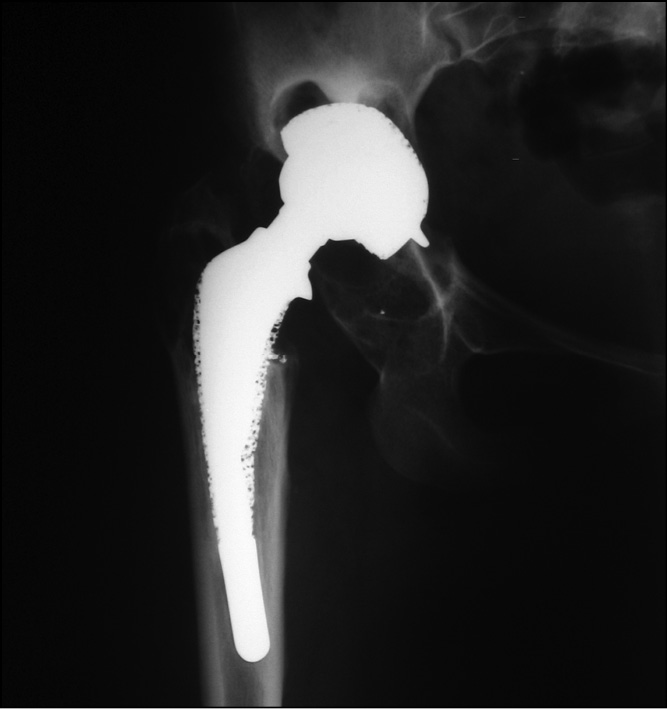

В 2001 г. по поводу левостороннего диспластического коксартроза в условиях 2-го отделения ЦИТО выполнено первичное тотальное эндопротезирование левого тазобедренного сустава (рис. 3, 4).

Рис. 4. Рентгенограмма левого тазобедренного сустава после первичного эндопротезирования в 2001 г.